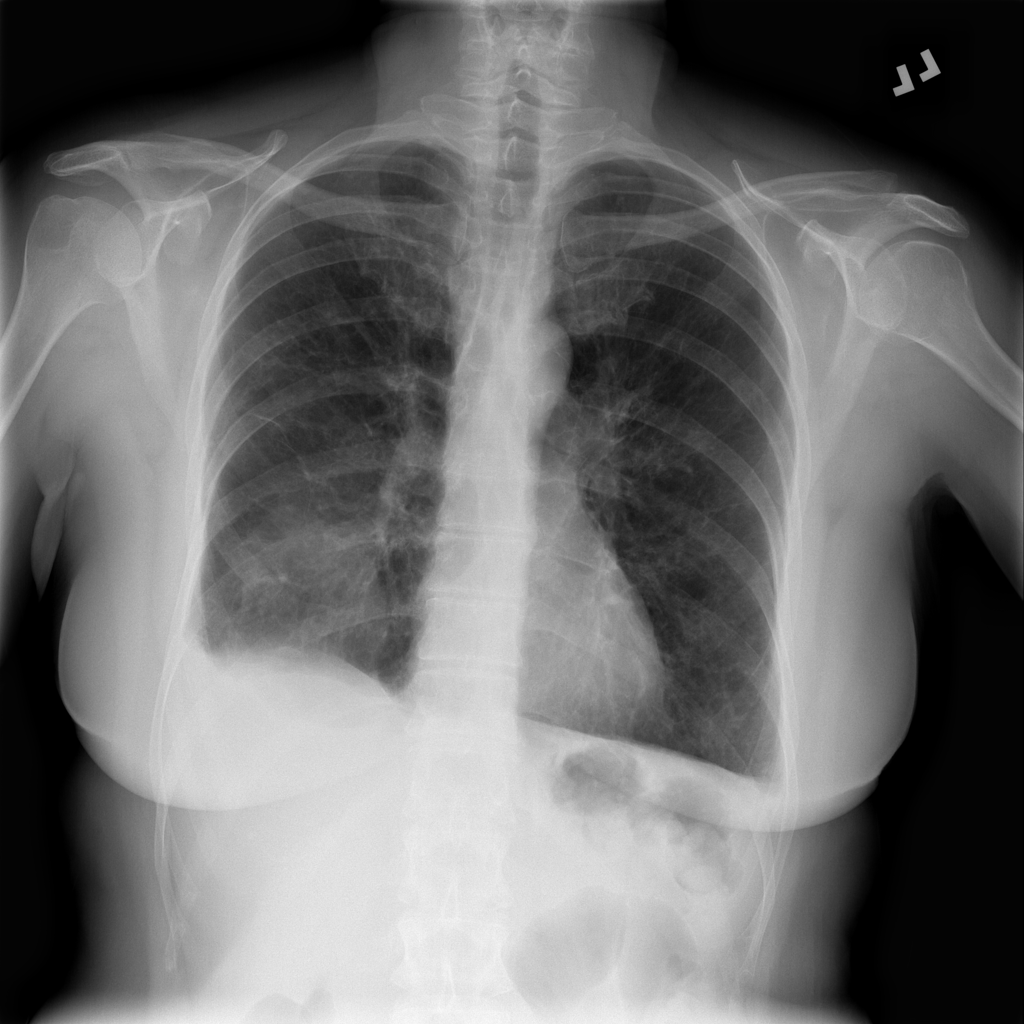

PAT-1F50 · IMG-000Fibrosis

PAT-1F50 · IMG-000

PA